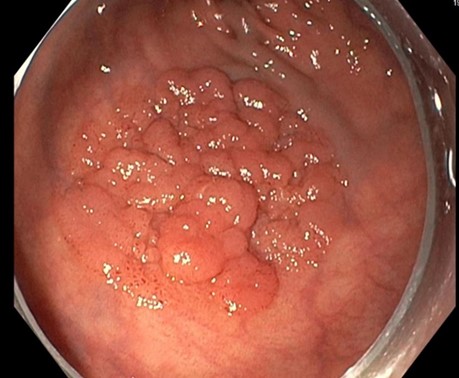

Bei einer Darmspiegelung wurde bei einem Patienten ambulant ein etwa 3 cm großer, flacher Polyp (Abbildung 1) im Enddarm (Rektum) entdeckt und der Patient uns zur endoskopischen Entfernung vorgestellt.

Der etwa 3 cm große Polyp konnte erfolgreich vollständig und zusammenhängend entfernt werden (Abbildung 4). Eine Operation war nicht erforderlich. Das entnommene Gewebe wurde anschließend feingeweblich untersucht, um die genaue Diagnose festzulegen.